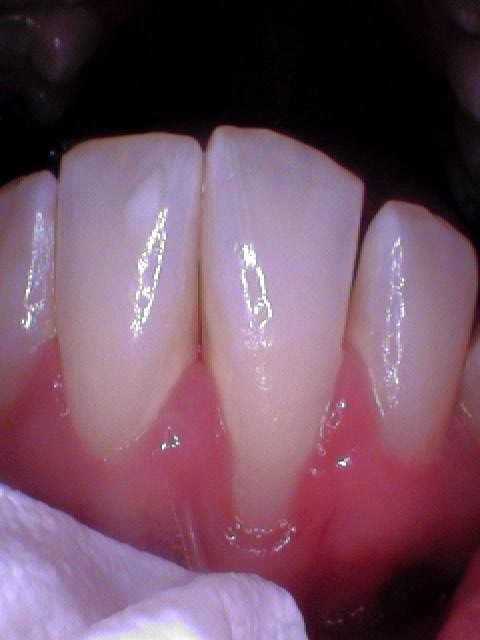

More than half of Americans have some form of gum disease. In the following photos, you can see tartar/plaque on the teeth and inflammation of the gums before periodontal therapy and cleaned tooth surfaces and healthy gums.

In these photos you can see the tenacious calculus on the lower front teeth. This calculus or tarter cannot be removed with brushing and flossing.